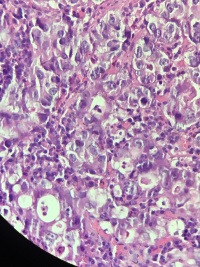

胃角溃疡活检

性别

男

年龄

68

临床诊断

胃角溃疡?

一般病史

反复胃痛1月余

标本名称

大体所见

灰白组织3块,直径0.1cm

老师帮忙看看,是溃疡还恶性?

黏膜内癌

乳头状管状腺癌